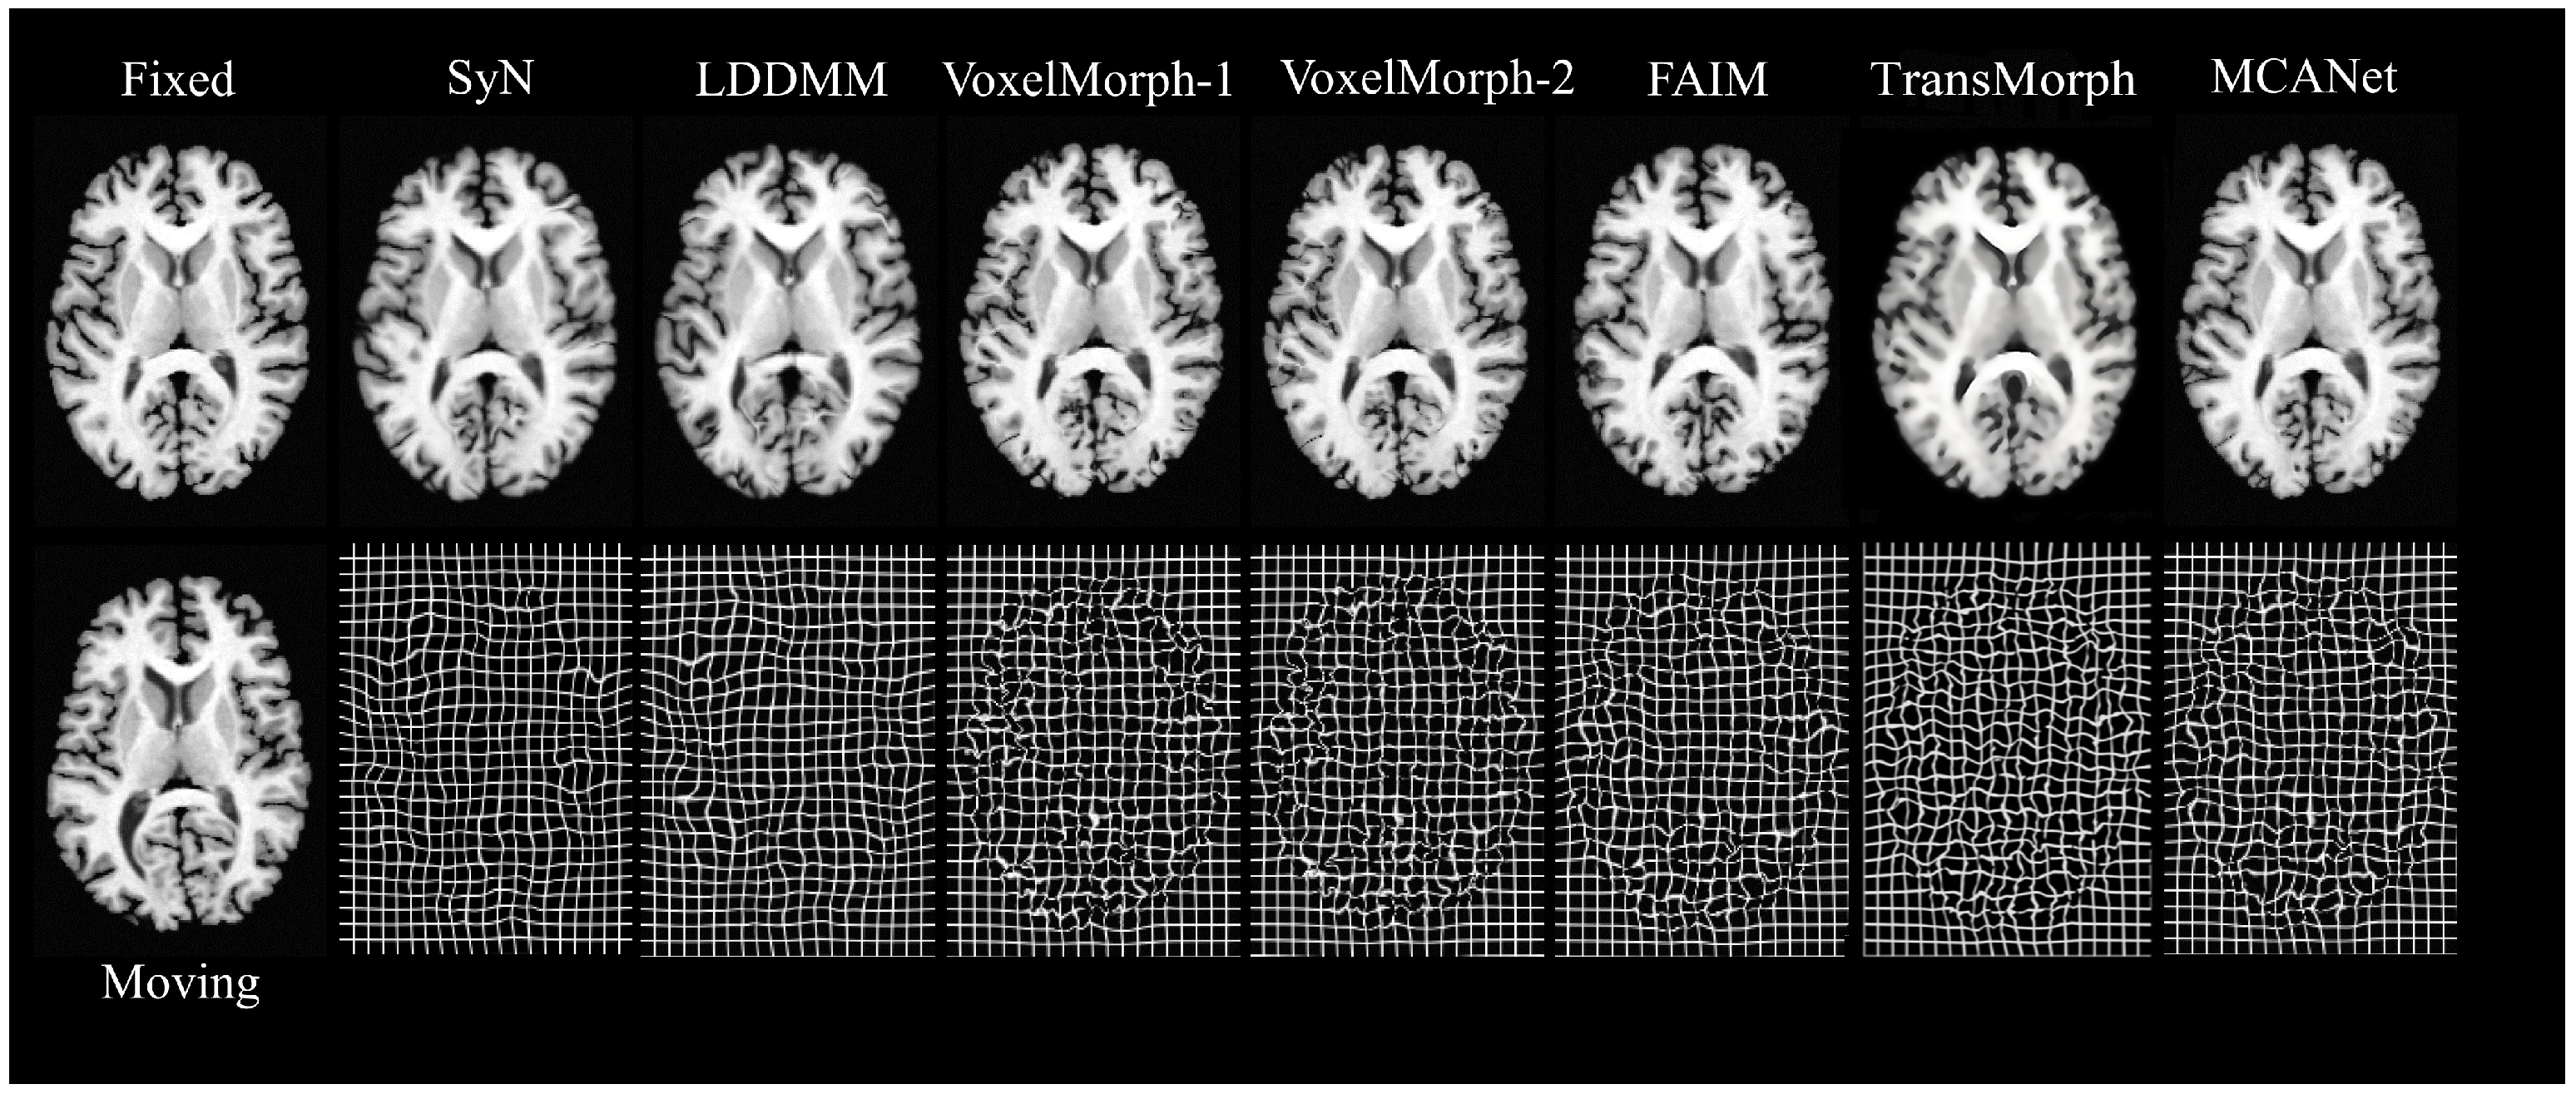

While traditional algorithms exhibit advantages in deformation field smoothness, this performance is contingent upon meticulous parameter tuning. Our experiments reveal that, as the gradient step in SyN increases, registration accuracy improves, but so does the deformation field folding rate, increasing linearly. This indicates that traditional algorithms may generate overly complex and uninterpretable deformation results with higher parameter settings. In contrast, MCANet not only surpasses traditional algorithms in registration speed but also in accuracy. Among the deep-learning methods, although MCANet often achieves higher or comparable Dice scores, it is not without drawbacks. Deep-learning algorithms typically require substantial training data and computational resources, and their performance can be sensitive to variations in data distribution. In comparison with Transmorph and DIF-VM, MCANet usually obtains higher or comparable Dice scores as well as lower SDlogJ, which indicates that MCANet usually has higher accuracy and smoother deformation fields. Deep-learning algorithms typically require large amounts of training data and computational resources, and their performance is very sensitive to changes in data distribution. Thus, the complexity of these models sometimes leads to longer training times and higher hardware requirements. Despite these challenges, MCANet achieves an optimal balance, efficiently delivering highly accurate and natural registration results. As shown in Figure 5, MCANet generates the most accurate and visually appealing alignment results on cross-sectional slices of the brain, effectively reconciling the trade-off between accuracy and computational efficiency.

Figure 5. Visualization results of several registration methods employed in this paper. The first row shows the fixed image and the deformed images warped by SyN, LDDMM, VoxelMorph-1, VoxelMorph-2, FAIM, Transmorph, and MCANet. The second row shows the moving image and the gridded deformation fields produced By SyN, LDDMM, VoxelMorph-1, VoxelMorph-2, FAIM, Transmorph, and MCANet.